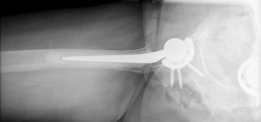

Femoral Preparation and Cementing Technique

Attention was then turned to the femur. The proximal femur was elevated and externally rotated. The femoral canal was entered using a box osteotome, taking care to lateralize the entry point into the greater trochanter to avoid varus malpositioning of the stem.

The canal was sequentially broached using a collarless, polished, double-tapered stem system. In a cemented technique, the broach size determines the size of the cement mantle, not the press-fit of the stem. A line-to-line broaching technique was used to allow for a uniform 2mm cement mantle.

Modern, third-generation cementing techniques are mandatory to ensure long-term survivorship and minimize the risk of Bone Cement Implantation Syndrome (BCIS). The steps performed included:

7. Stem Insertion: The polished, double-tapered stem was inserted in the correct version (approximately 10-15 degrees of anteversion) and held rigidly until the cement fully polymerized.

Following final stem cementation, the definitive femoral head (typically a 32mm or 36mm ceramic or cobalt-chrome head, depending on the cup size) was impacted onto the trunnion. The hip was reduced, and final stability checks were performed.